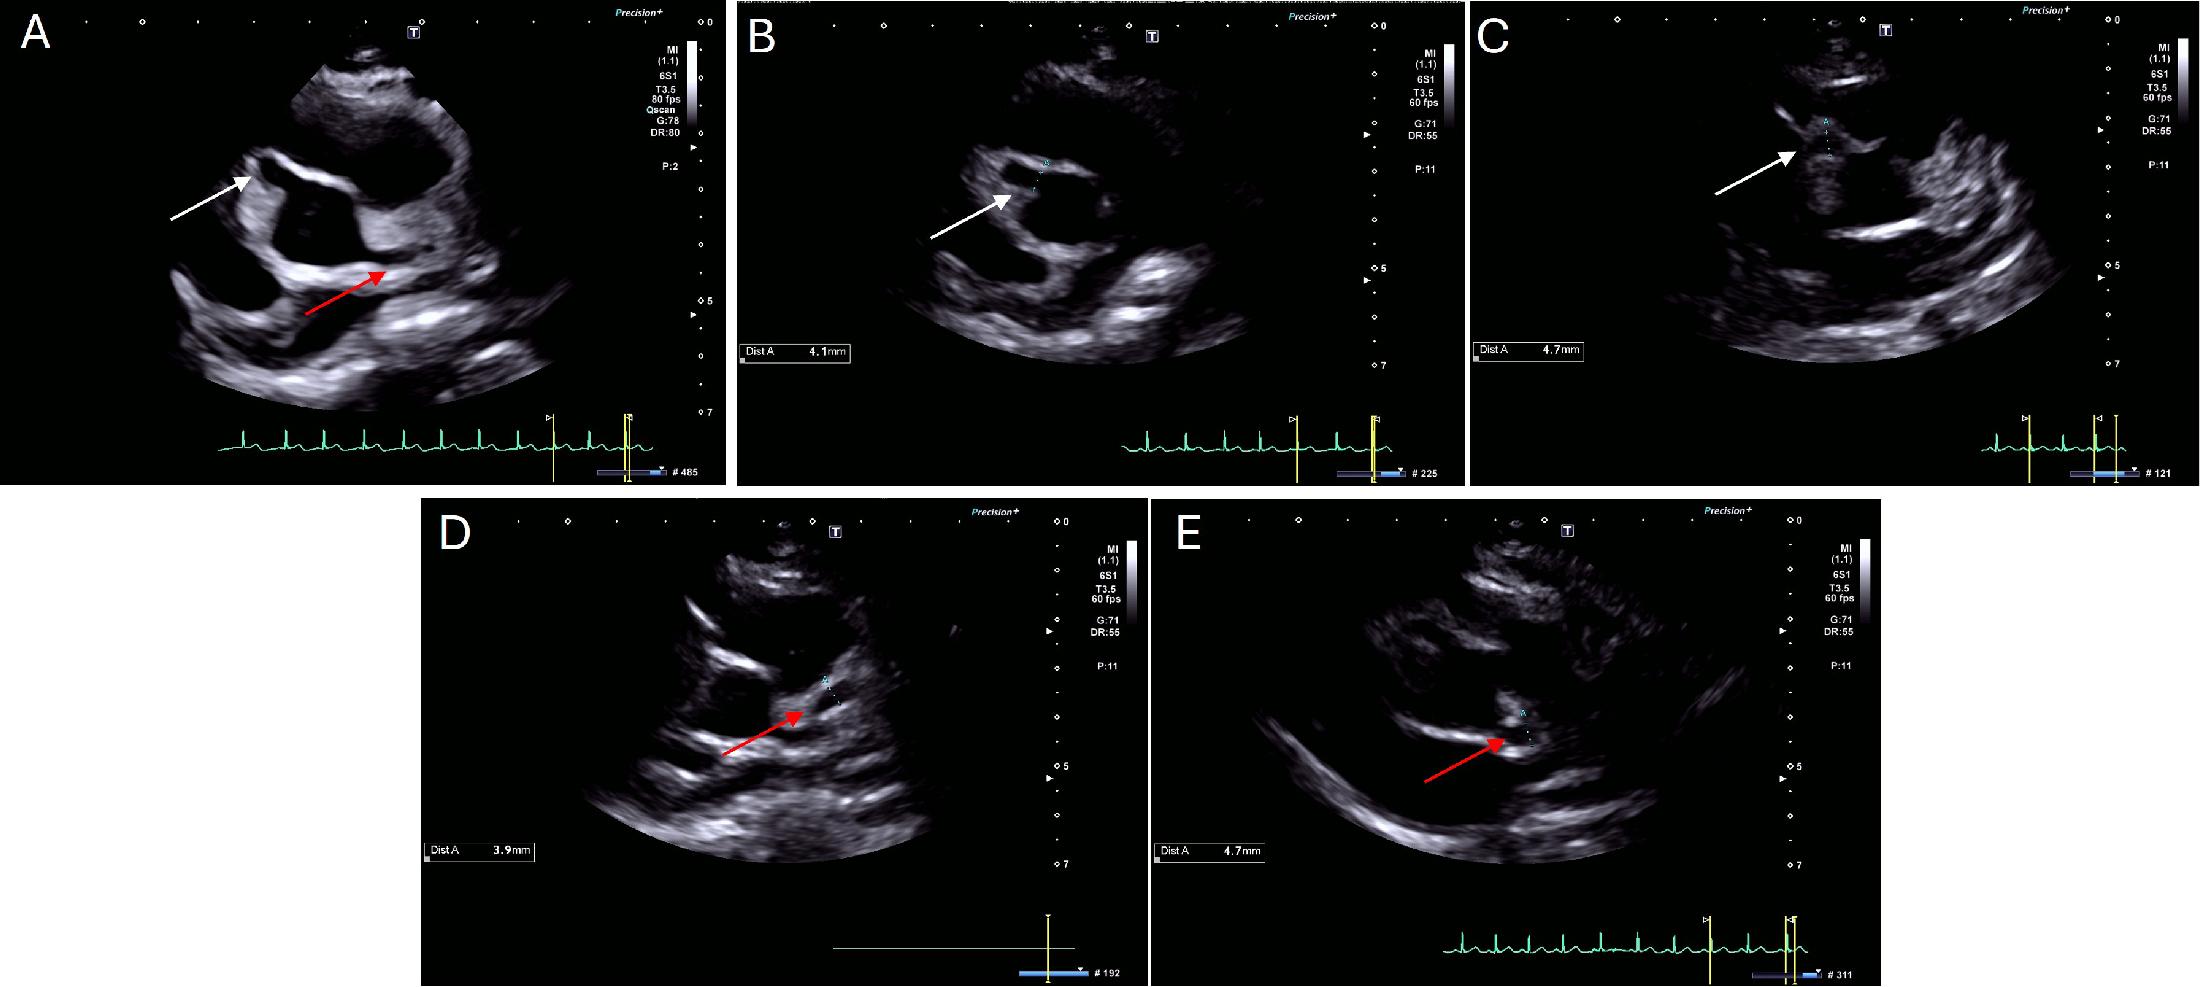

On arrival, ECG demonstrated sinus tachycardia with a normal repolarization pattern (Figure 1). The TTE revealed a medium aneurysm of the RCA (Figure 2, Panel A-C), with a diameter of 5 mm (Z-score +7.8). The LMCA origin measured 3 mm (Z-score +1.6), and the proximal trunk of the LMCA (Figure 2, Panel D-E) measured 4 mm (Z-score +4.5). At the bifurcation of LMCA, a large aneurysm with a maximum diameter of approximately 8 mm (Z-score +10) was identified, with suspected thrombotic material observed within its lumen. The anterior descending artery (LAD) demonstrated a maximum diameter of 4 mm (Z-score +9). Given this suspicion of intracoronary thrombus, IV heparin was started, together with the overlapping of warfarin therapy until the INR was within the therapeutical range. Cardiac computed tomography (CCT) confirmed the coronary aneurysms, without evidence of intraluminal thrombi (Figure 3, Panel A-D).

Transthoracic echocardiography in the parasternal short-axis view showing a right coronary artery aneurysm (Panel A, white arrow) and a left main coronary artery aneurysm (Panel A, red arrow). The proximal portion of the right coronary artery (Panel B, white arrow) has a diameter of 4.1 mm (Z-score +7.4), while the distal portion of the right coronary artery (Panel C, white arrow) has a diameter of 4.7 mm (Z-score +7.8). The left main coronary artery bifurcation (Panel D, red arrow) measured 3.9 mm (Z-score +4.9), while the proximal left anterior descending artery (Panel E, red arrow) measured 4.7 mm (Z-score +8.1).